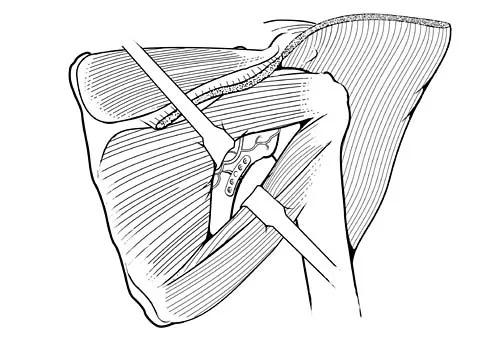

During a posterior approach to the glenoid with retraction as shown in Figure 33, care should be taken during superior retraction to avoid injury to which of the following structures?